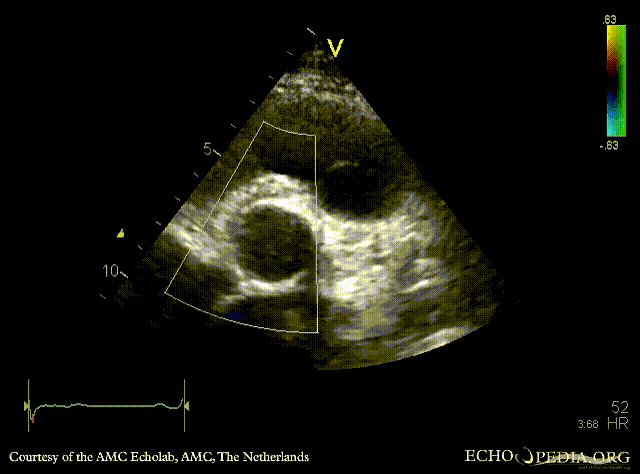

Davids procedure

Courtesy of: AMC Echolab, AMC, The Netherlands

PSAX: native aortic valve and prosthesis in ascending aorta PSAX with Color Doppler